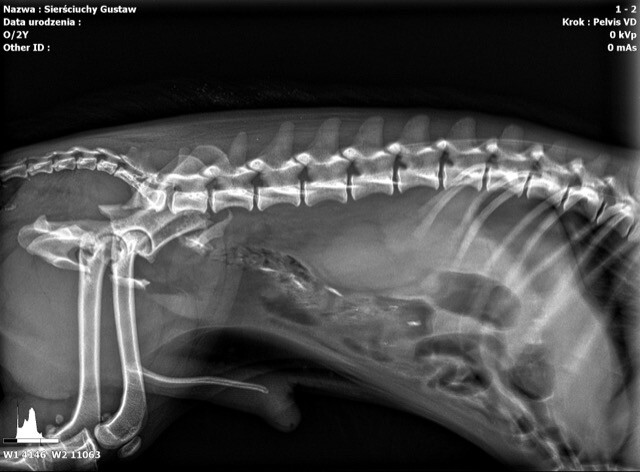

Sam złamałem jednak coś innego... Leżałem pod tujami. I nie to, że nie chciałem wstawać, że byłem zmęczony, że „na kanapie siedzi leń, nic nie robi cały dzień”. Nic z tych rzeczy. Pan psi doktór, tzn. wiecie, ten taki w fartuchu, co zwierzęta leczy, zrobił mi prześwietlenie. Mówię wam, to była przygoda. Czułem się jak prawdziwy gwiazdor, psi celebryta. Jeszcze mi zdjęcia robili...

Okazało się, że mam złamaną miednicę. No, nie powiem, nic przyjemnego. Dostałem leki, miałem operację i dobrze mi poszło. Pomocną łapę podało mi Stowarzyszenie Przytul Sierściucha z Myślenic. Co dalej? Usłyszałem niesamowitą historię o moim koledze. Ten to ma dopiero imię... I do tego złamaną łapę.

fot. Stowarzyszenie Przytul Sierściucha